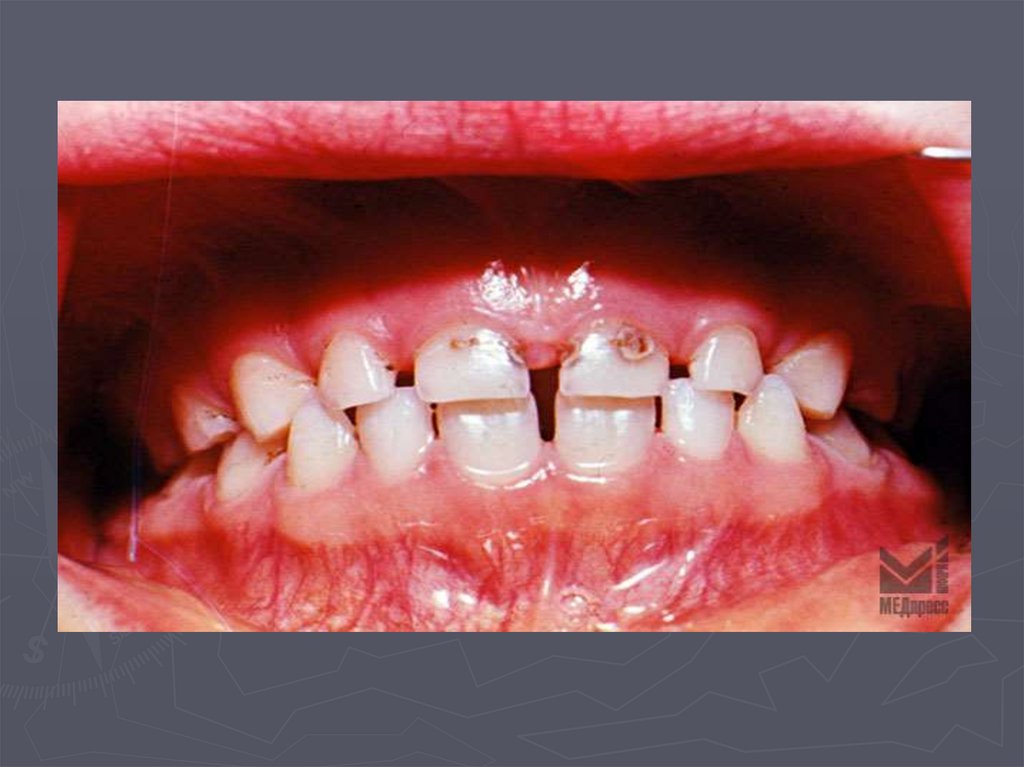

4. ОСОБЕННОСТИ КЛИНИЧЕСКОГО ПРОЯВЛЕНИЯ КАРИЕСА У ДЕТЕЙ РАННЕГО ВОЗРАСТА

У детей в возрасте от 1года до 3 лет КАРИЕС

чаще возникает:

► на зубах, имеющих порочно развитые ткани в виде

гипоплазии;

► ткани этих зубов недостаточно минерализованы;

► чаще поражаются резцы;

► затем моляры и клыки;

► преимущественная локализация кариозной полости на

вестибулярной и контактной поверхности резцов ;

► а также в фиссурах моляров;

► нередко кариес начинается в пришеечной области;

► процесс распространяется вокруг всей коронки;

► формируется циркулярный кариес.

8. Циркулярный кариес